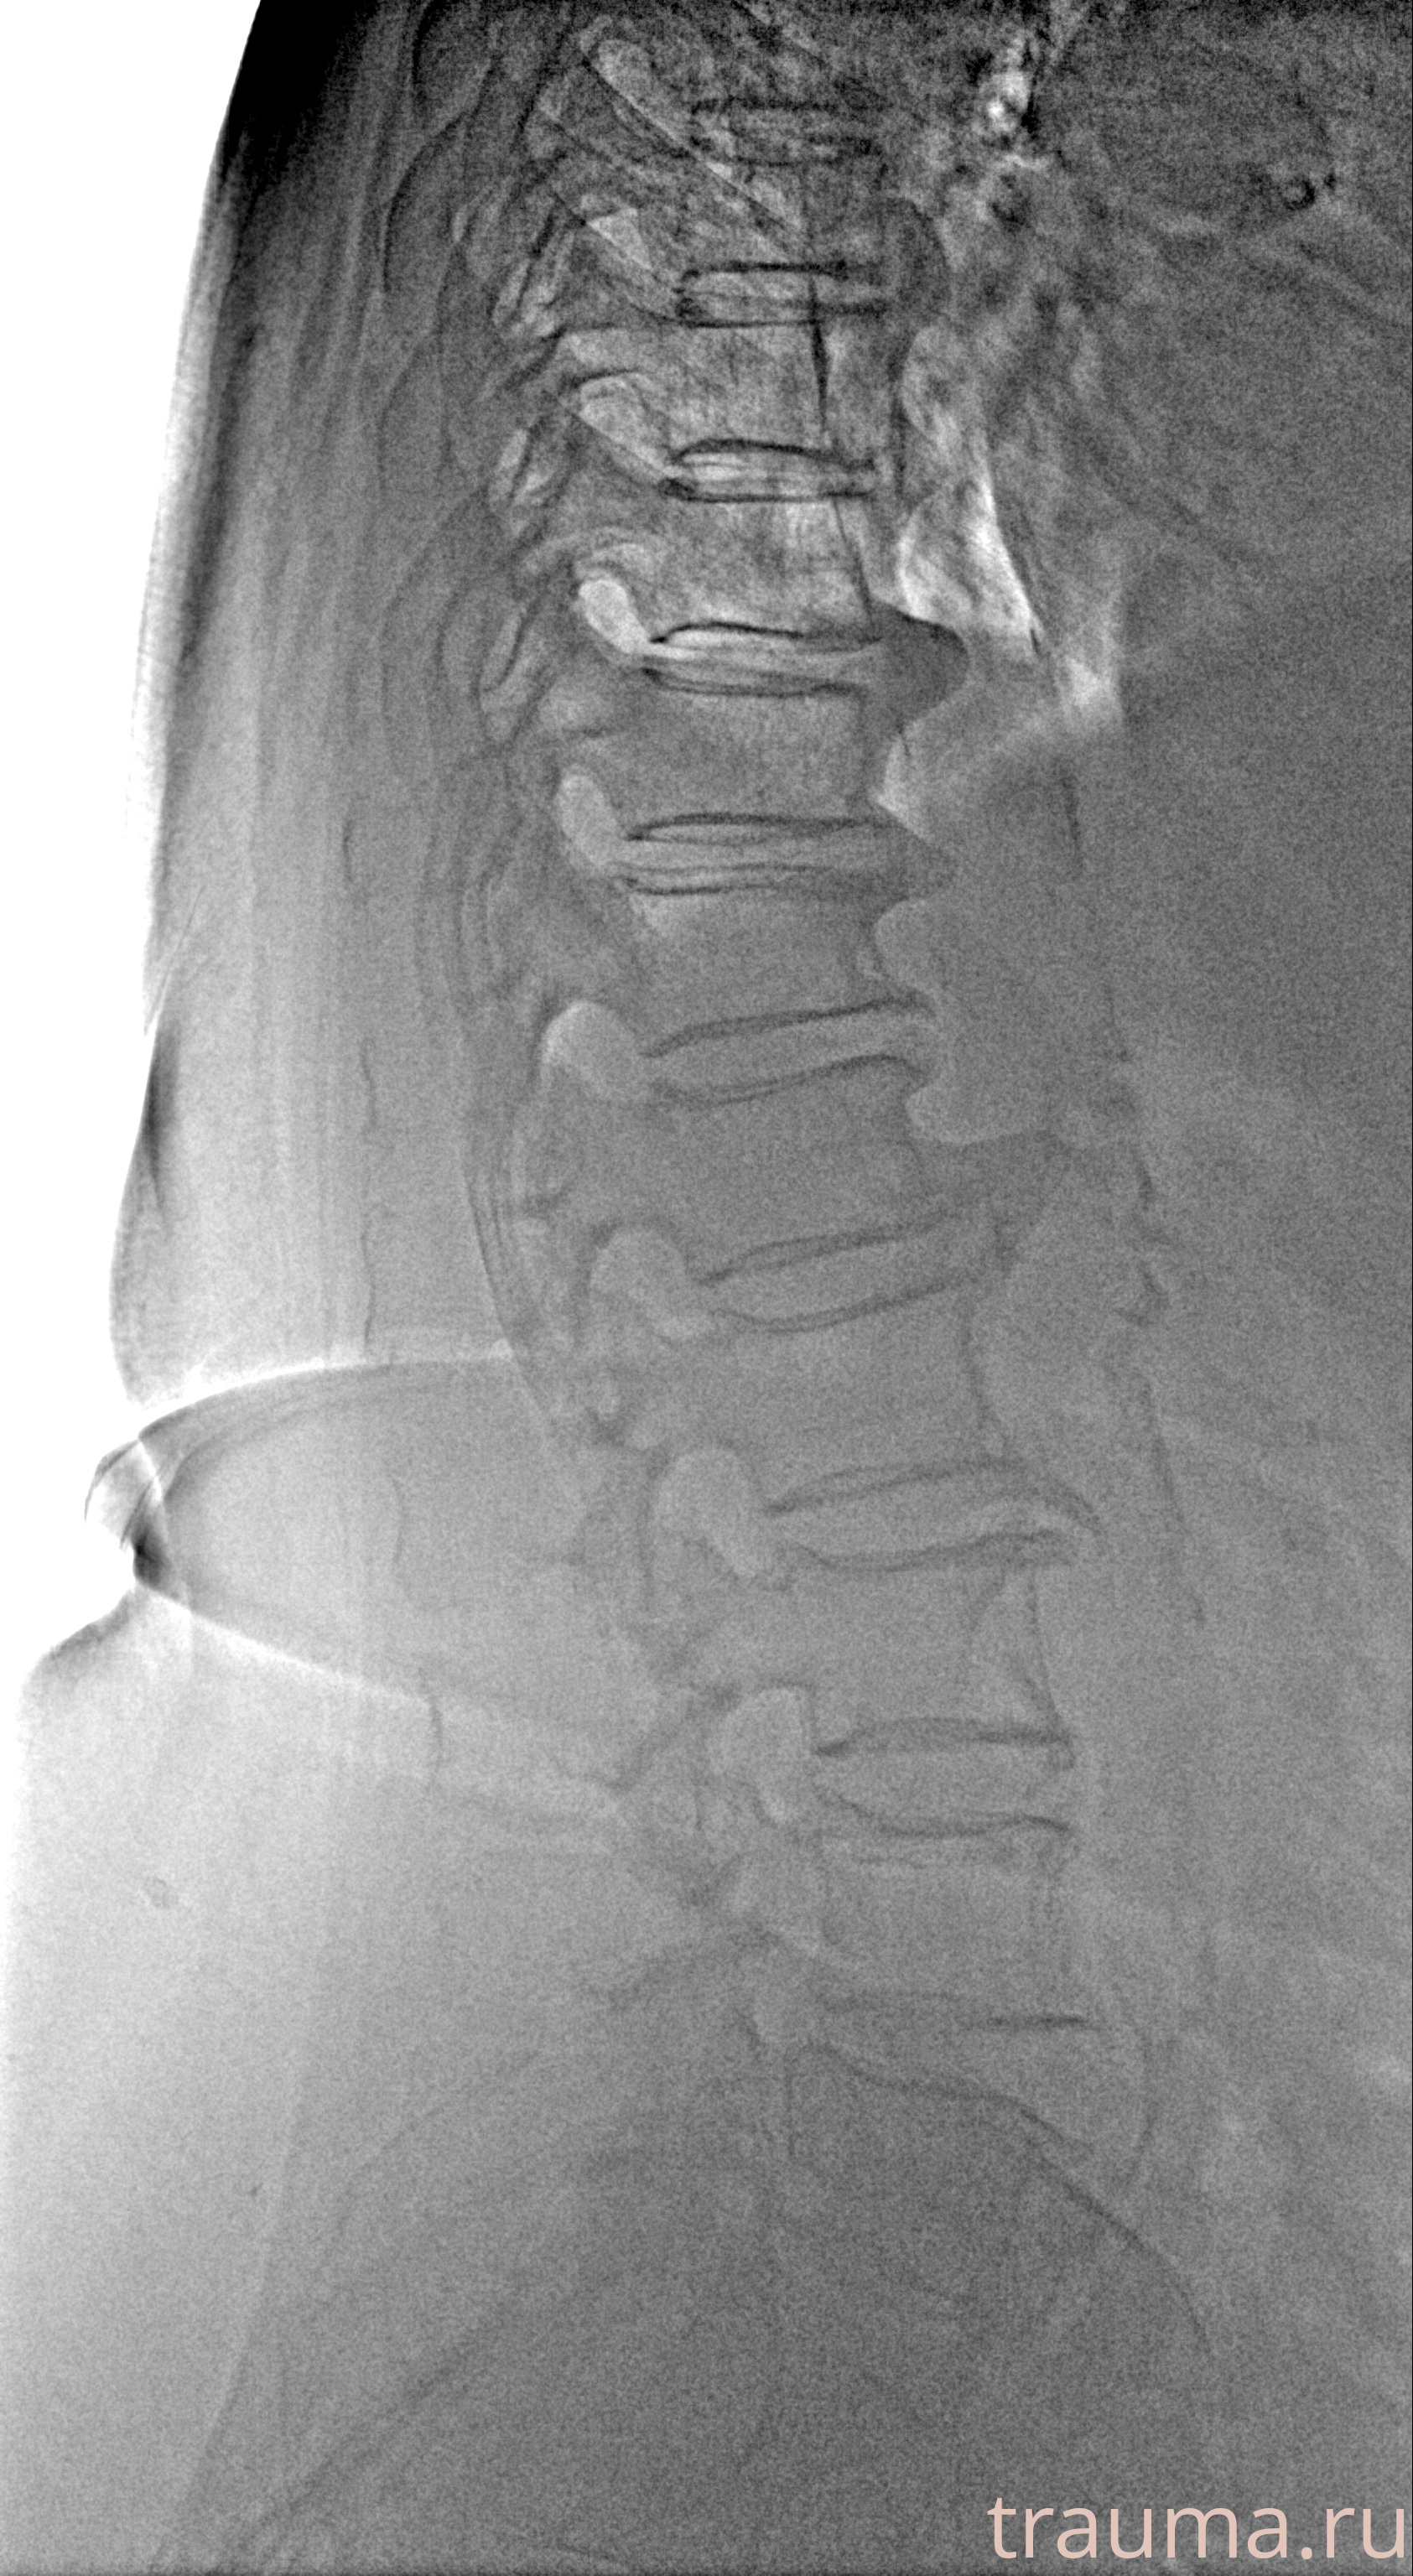

Рентген на дому: по вашему адресу приезжает врач-рентгенолог, травматолог-ортопед с мобильным рентгеновским аппаратом, проводит диагностику травмы или заболевания, делает необходимые рентгенограммы, дает рекомендации по дальнейшему лечению. Получить качественные снимки в домашних условиях возможно благодаря уникальной методике, разработанной МосРентген Центром для института  Склифосовского